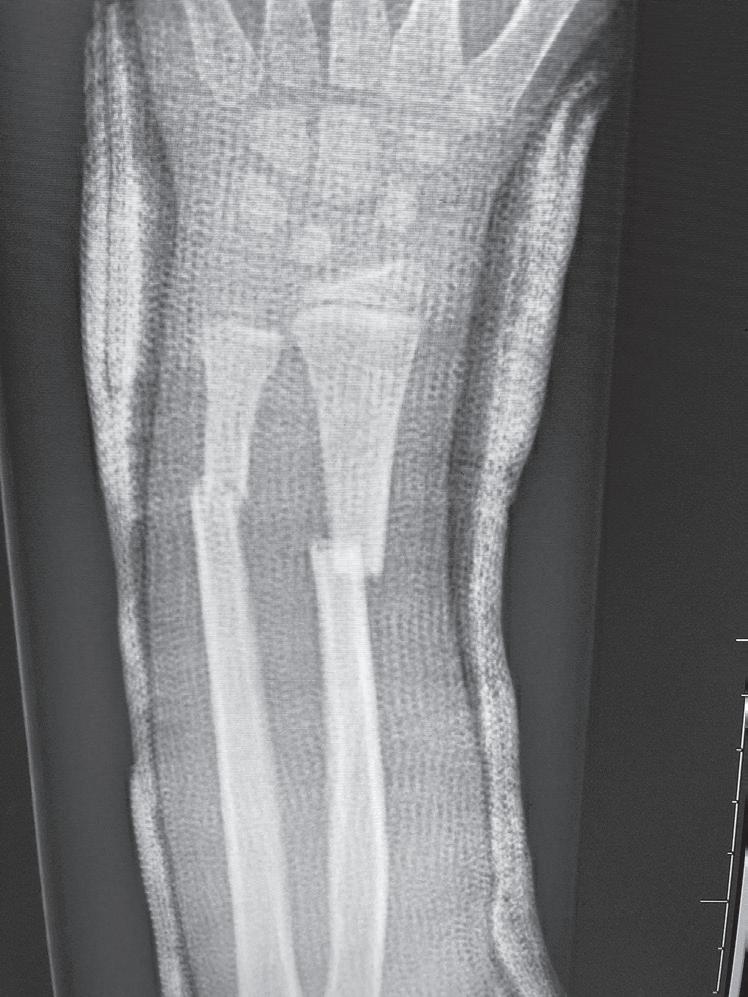

Secondary healing results from treatment of fractures with less rigid methods (i.e., fracture bracing, casts). In secondary healing, more motion at the fracture site leads to lower

Fig. 1.2 Anteroposterior (A) and lateral (B) radiographs of a forearm in a 15-year-old male who underwent open reduction and internal fixation with plates/screws. The fracture healing demonstrates primary bone healing with rigid fixation. An anteroposterior radiograph of a forearm in a 5-year-old at the time of original cast immobilization (C) and at 10 weeks (D) with complete fracture union demonstrates secondary bone healing. The motion that occurs with secondary bone healing results in abundant callus formation.

oxygen tension, and more cartilage is formed. Motion at the fracture site, the presence of a fracture gap, and an intact soft tissue envelope all encourage the formation of abundant callus (Fig. 1.2C, D). The increased diameter of the callus enhances biomechanical stability because the rigidity of the bone is proportional to its radius. The callus formed subsequently undergoes endochondral ossification. Ideal fracture treatment involves enough rigidity to ensure adequate vessel ingrowth, followed by progressive loading and motion to stimulate ample callus formation.36,40